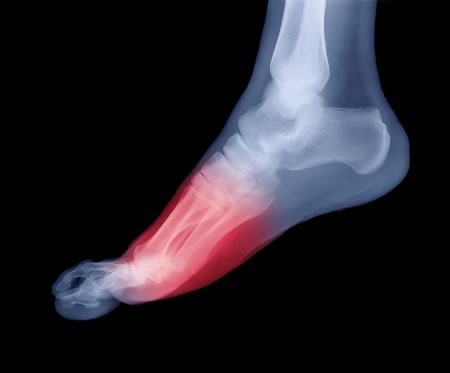

3- ألم الكعب:

السبب الأكثر شيوعا لألم الكعب هو التهاب الرباط الأخمصي. قد يكون الألم حادا عندما تستيقظ أوبالضغط على القدم. التهاب المفاصل وممارسة الرياضة المفرطة ، والأحذية السيئة يمكن أيضا أن تسبب ألم الكعب.والأسباب الأقل شيوعا تتضمن والتهاب العظام والأورام، أو الكسور